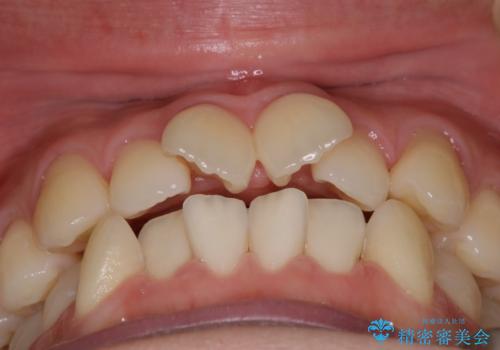

- 上の前歯のデコボコが気になるということで来院されました。

叢生量(デコボコ)が多いため、上下左右4番目の歯を抜歯してワイヤー矯正を行う治療計画を立てました。